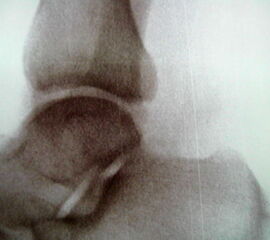

Reseziertes Os trigonum sowie prä- und postoperatives seitliches Röntgenbild nach arthroskopischer Entfernung eines Os trigonum.

Knochenresektat sowie präoperatives CT (Sagittal- und Transversalebene) und intraoperative Bildwandlerkontrolle im seitlichen Strahlengang nach arthroskopischer Entfernung multipler Ossikel am dorsalen OSG/USG.

Große osteophytäre Anbauten, welche die FHL-Sehne vollständig ummauern, sind ebenfalls sehr gut in der beschriebenen Technik adressierbar. Präoperatives CT und intraoperative Bildwandlerkontrolle im seitlichen Strahlengang (linke Seite).